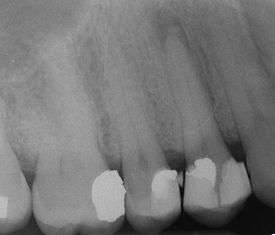

This radiograph shows significant bone loss between the two roots of a tooth (black region). The spongy bone has receded due to infection under tooth, reducing the bony support for the tooth. | |